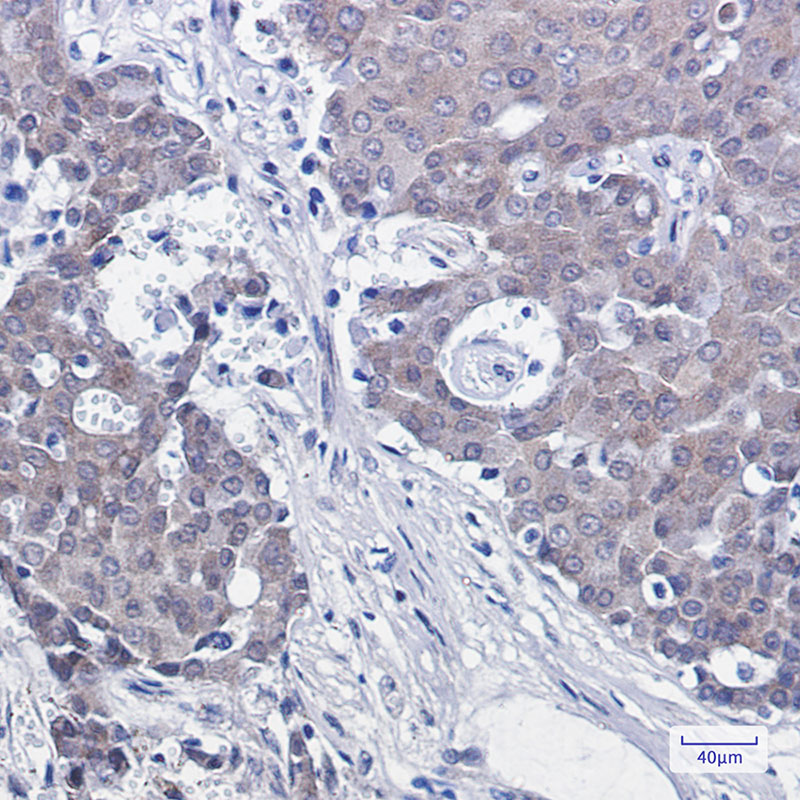

Immunohistochemistry analysis of paraffin-embedded Human breast cancer using NEDD8 antibody. High-pressure and temperature Sodium Citrate pH 6.0 was used for antigen retrieval.